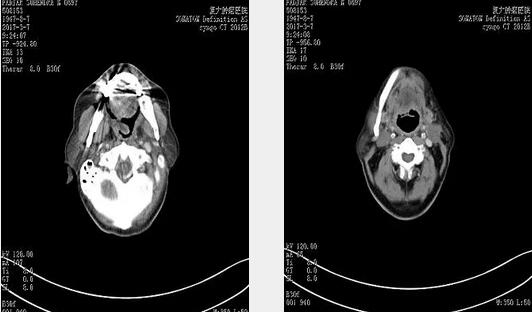

2017年3月7日2次消融后CT,左侧扁桃体肿瘤明显退缩。